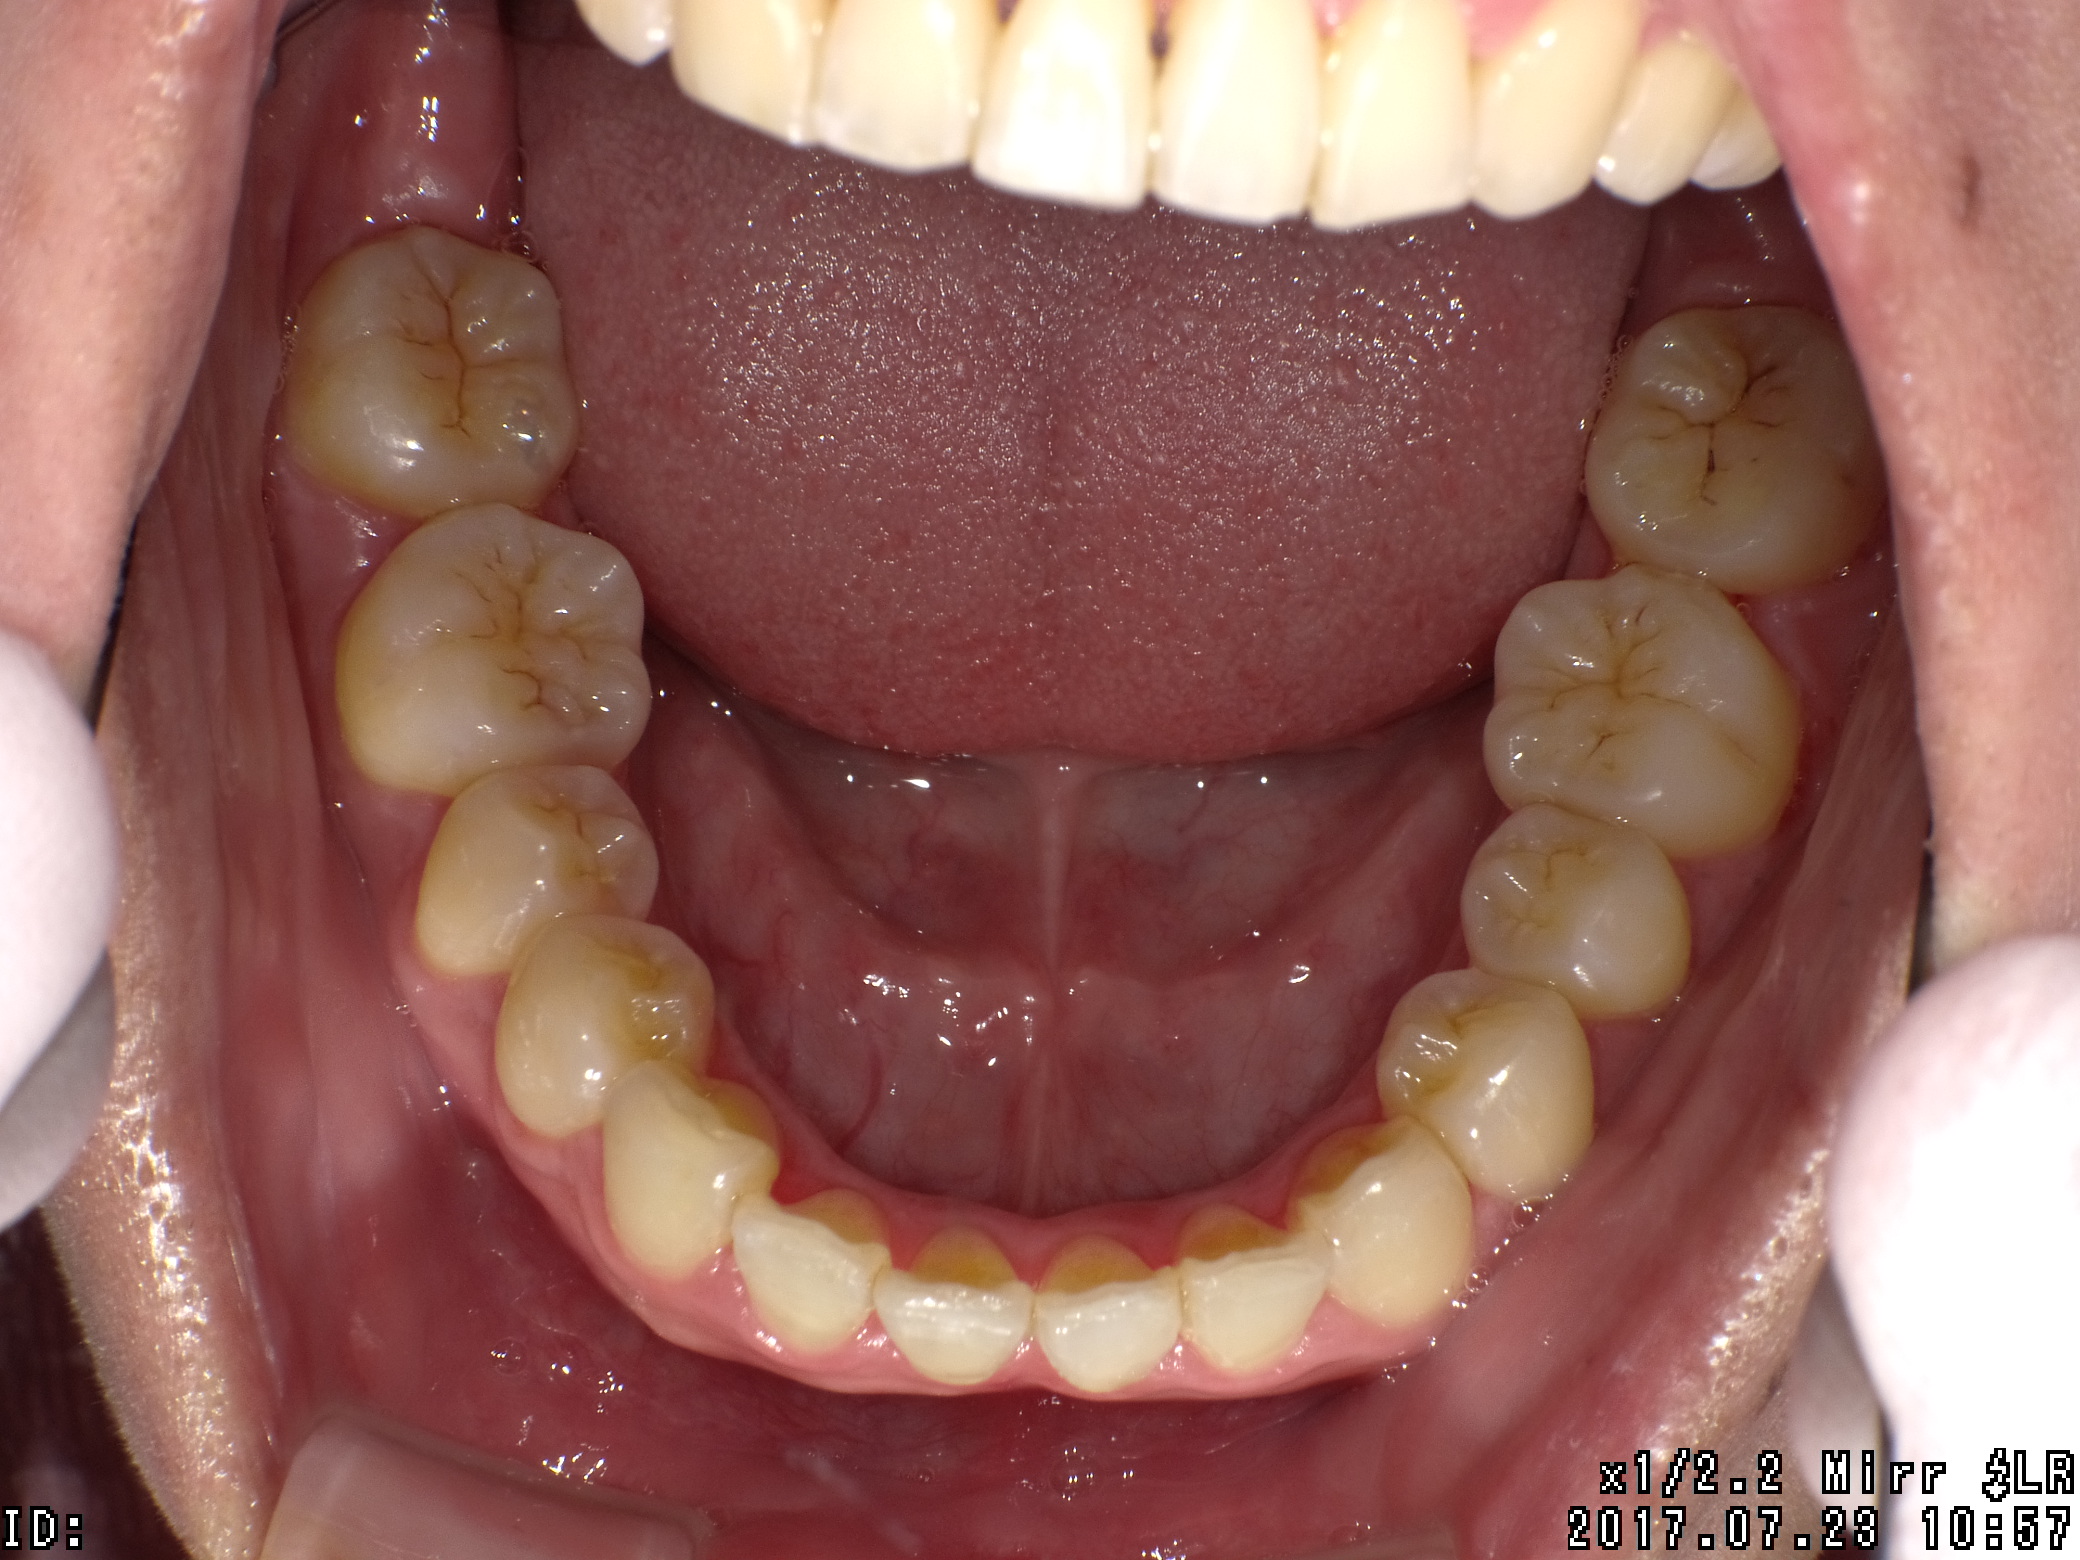

| 治療期間 | 2017年04月 〜2019年08月 |

|---|---|

| 治療費用 | 約700,000円 |

| 抜歯有無 | 抜歯有り |

| 矯正箇所 | 上顎・下顎 |

| 治療のリスク | 治療の過程で使用する針金やゴムにより、違和感や不快感を感じたり、口内炎になることがあります。 |